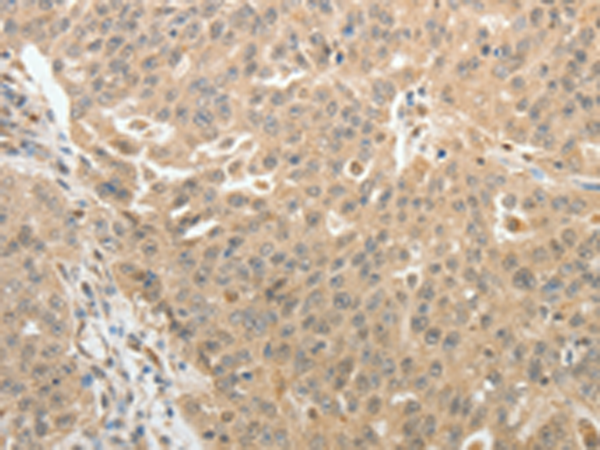

分类: 科研抗体货号: P11132别名: MAP-2; Mtap2; Mtap-2应用: IHC反应种属: Human, Mouse, Rat